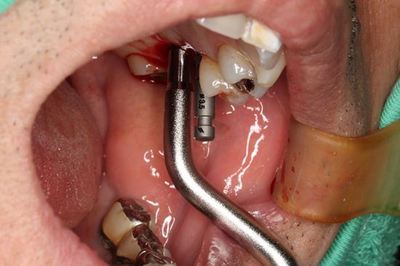

ここからはソケットリフトを行いますのでオステオトームで上顎洞を挙上します。

オステオトームでのソケットリフトを終えました。

正確な位置でインプラント床を拡大するために粘膜剥離をせずに行います。

骨の柔らかい方向へオステオトームが逃げますので粘膜をガイドにして

拡大していきます。

骨の上部は必ずドリルで形成します。